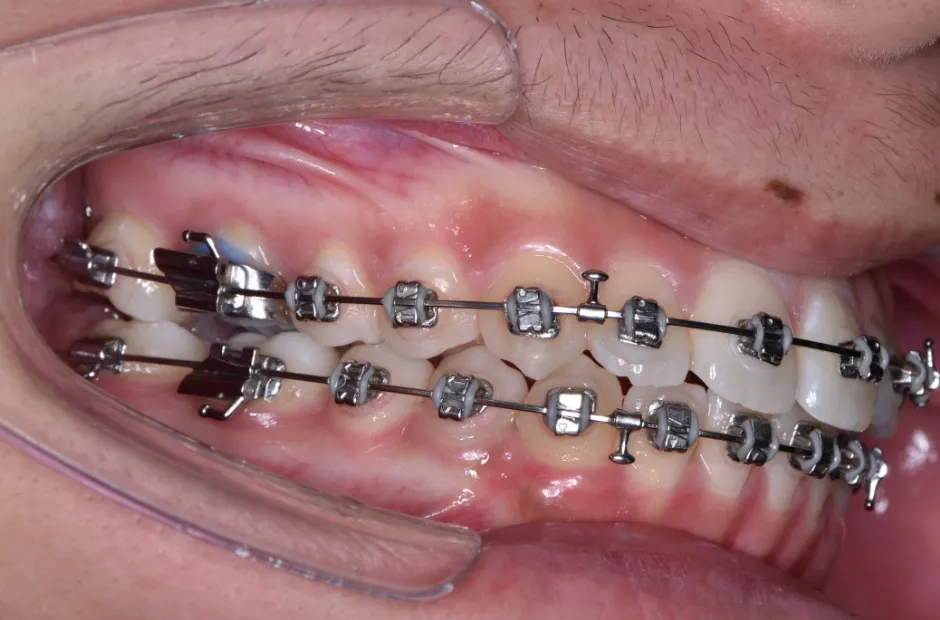

治療中